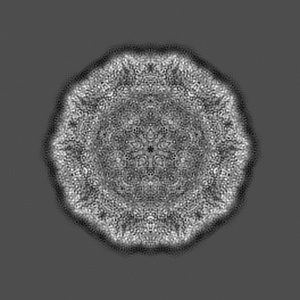

CryoEM structure of human enterovirus D68 expanded 1 particle (pH 6.5, 4 degrees Celsius, 3 min)

Sample Organism: Enterovirus D68

Sample: Enterovirus D68

Molecular basis for the acid-initiated uncoating of human enterovirus D68.

Liu Y , Sheng J, van Vliet ALW, Buda G, van Kuppeveld FJM , Rossmann MG

(2018) PNAS , 115 , E12209 - E12217